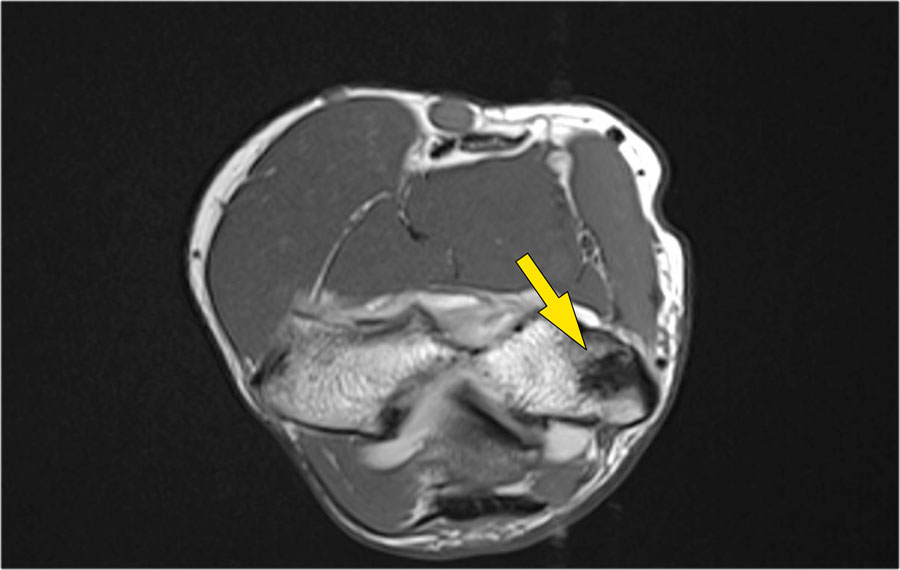

Những hình ảnh này của một nam giới 23 tuổi bị ngã chống tay khi đang trượt ván hai tuần trước.

Khi khám lâm sàng, ghi nhận giảm biên độ vận động khớp khuỷu và đau khi ấn dọc theo mặt ngoài.

Cấu trúc nào nằm phía sau chỏm quay trên hình ảnh cắt ngang?

Cấu trúc phía sau chỏm quay là dây chằng vòng.

Nó không đều và dày lên do hậu quả của trật khớp ra sau.